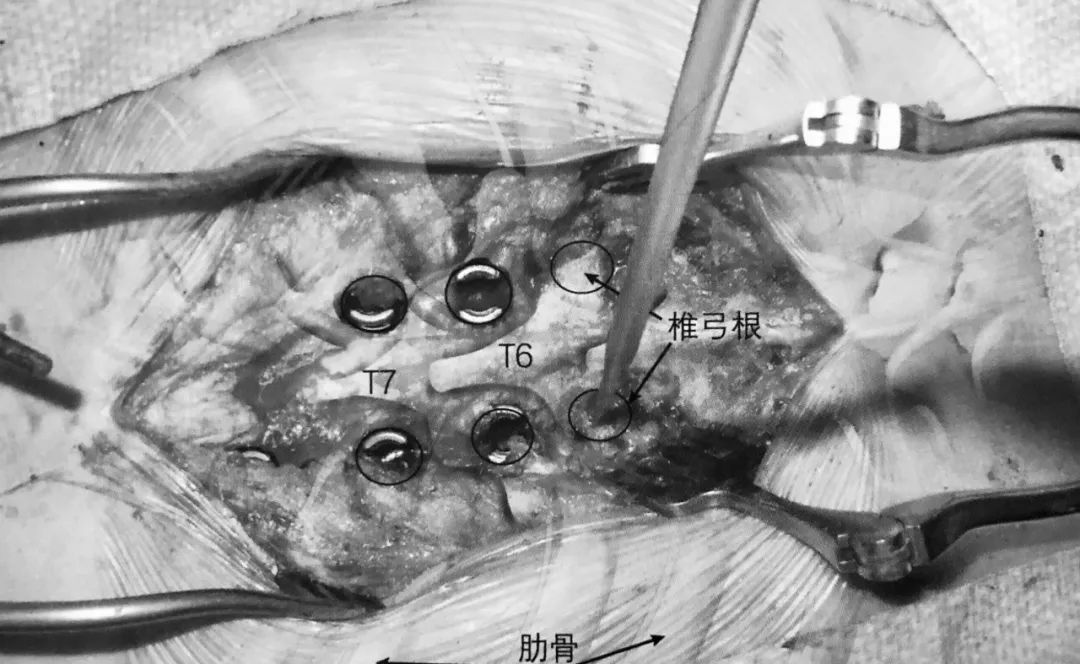

1. 术前准备要点:

2. 术中使用双平面透视机。

3. 球囊套管的开口点应位于椎弓根的 10 点或 2 点位置即上外侧角,取决于左右。将置入通道设计于该处可保证其离神经根最远。如前后位片所示插入通道,侧位片上套管通过椎体后缘线之前不能越过椎弓根内壁。

4. 通道开口点位于关节突关节外侧,这样可以避免损伤关节囊。

5. 术中透视证实球囊位于椎体前部,这可避免骨折块向后突入椎管。

6. 球囊充气为骨水泥注入建立潜在空间。

7. 透视下向椎体内注入骨水泥,在正侧位片上仔细观察以确保椎体边缘不被侵犯。如果发现骨水泥溢出,则停止注入。应避免将骨水泥注入椎体后部。

8. 理想情况下,正位片上骨水泥充填应该通过中线。

9. 潜在风险:

严重骨质疏松导致透视效果差

骨水泥栓塞

骨水泥向椎间孔或椎管溢出

套管置入不当引起椎弓根骨折

骨水泥充填不足

8. 潜在风险:

椎弓根钉侵犯内侧和下壁可能损伤神经根和脊髓

螺钉太长侵犯前方骨皮质可能导致血管或内脏损伤

椎弓根螺钉置钉位置不当可能引起螺钉拔出或固定失败